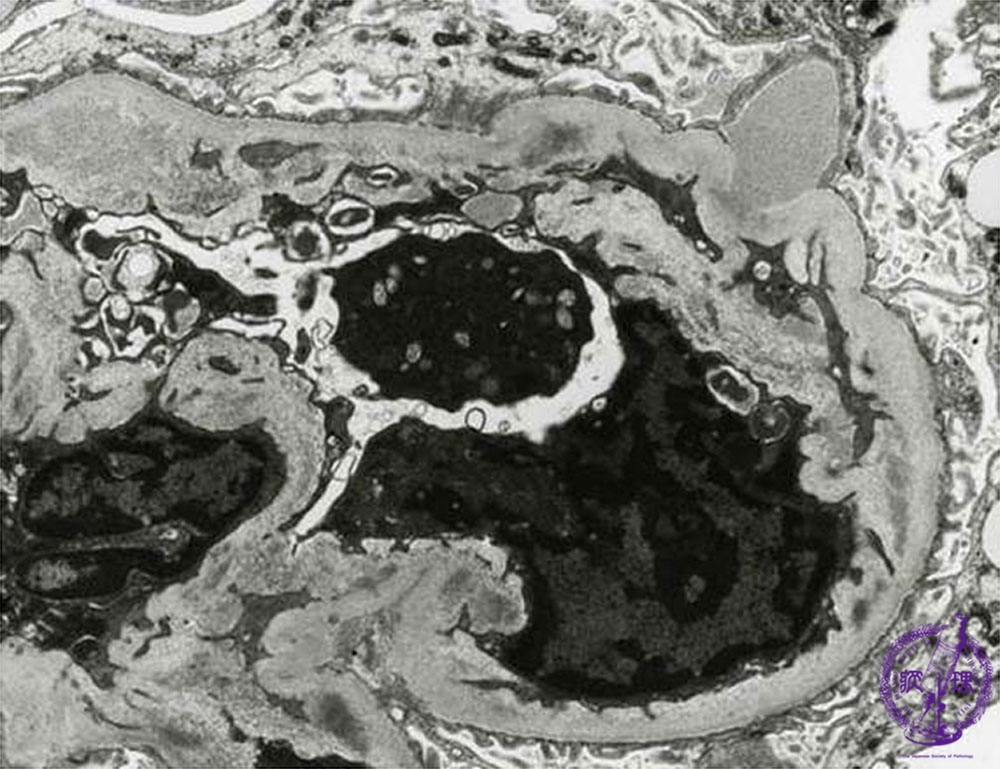

- (8)Endocapillary proliferative glomerulonephritis

Microscopic findings(electron microscopy): There are electron dense subepithelial deposits (yellow arrows). The deposits, known as humps, protrude predominantly from the subendothelial aspect.